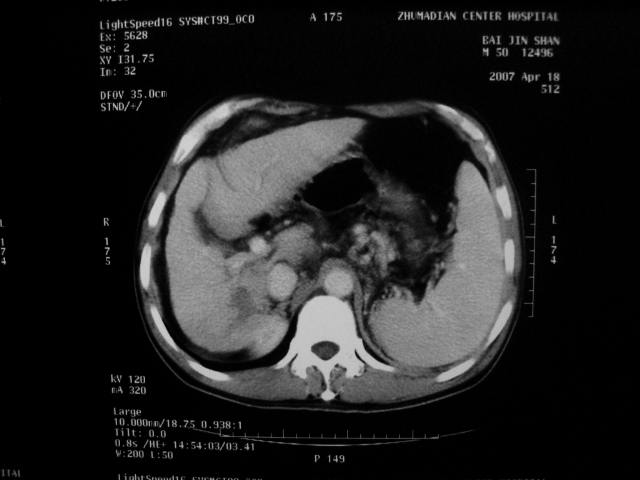

标题: CT7751:病人,50岁,肝硬化多年,行CT三期扫描 [打印本页]

标题: CT7751:病人,50岁,肝硬化多年,行CT三期扫描

动脉期病灶见轻度强化,考虑肝癌可能性大。

动脉期轻度强化 考虑 肝右叶小肝癌可能性大

肝硬化 脾大 胃底静脉曲张 肝癌 门腔间淋巴结肿大

1、肝右叶低密度灶考虑肝癌

2、肝硬化

肝硬化、脾大,静脉曲张,肝右叶低密度灶,增强无明显强化,还是考虑肝癌可能性大,建议结合afp检查。

考虑肝硬化,脾大,静脉曲张,肝右叶低密度灶,右肝癌可能性大。

肝癌分为肝细胞性和胆管细胞性,从强化表现来看,确切地说应是胆管细胞癌.